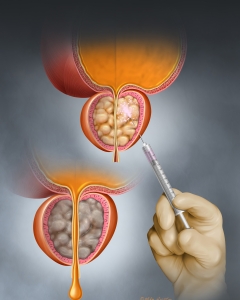

Internal Art Medical Illustration

Blending Art, Anatomy and Science for Creative Visuals

Patient & Professional Marketing

Welcome to my Patient and Professional Marketing page, where I harness the power of anatomical illustrations to educate and empower both patients and medical professionals. My unique approach combines artistry and education to convey complex surgical procedures and the utilization of medical devices in an easily understandable manner.